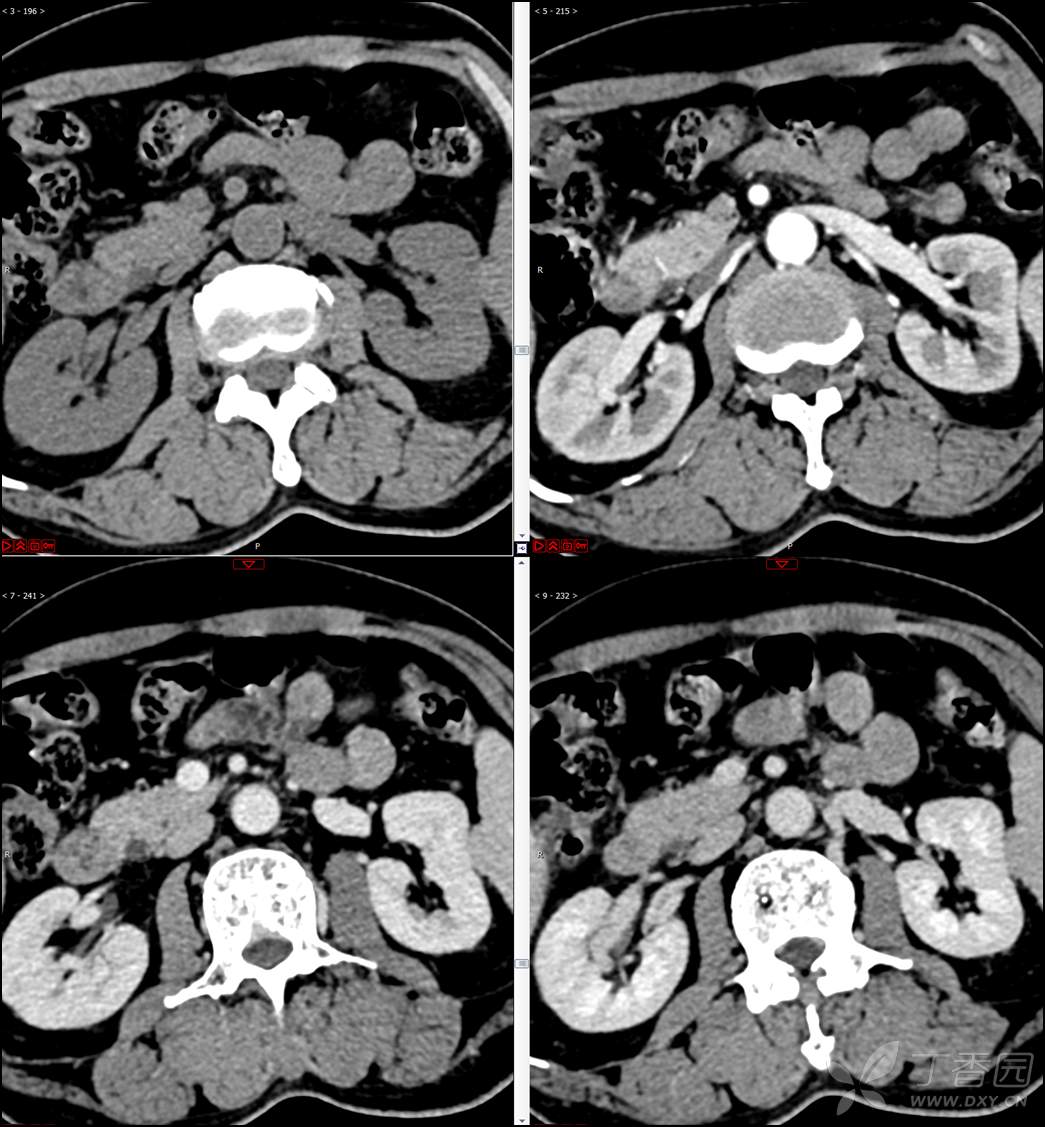

【影诊笔记521】老年男性,黑便就诊,请分析~『回帖即可查阅答案』

患者年龄:67岁

主诉:黑便1周。

现病史:患者1周前无明显诱因出现黑便伴头晕、心慌,无胸闷、胸痛,后仍间断黑便,2022-10-27就诊于某市中医院,行胃镜检查示:十二指肠溃疡伴出血,给予止血、抑酸等对症治疗,效果欠佳。今为行进一步治疗就诊于我院急诊,门诊完善新型冠状病毒核酸检测后以“十二指肠溃疡伴出血”收入我科。患者自发病以来,神志清,精神可,未进食,睡眠可,小便未见异常,黑便,近期体重无明显增减。